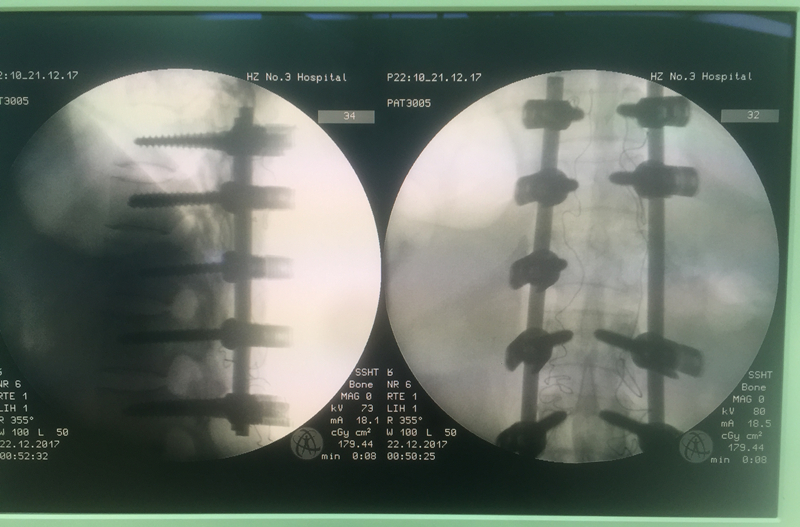

在手術(shù)過程中,醫(yī)生們發(fā)現(xiàn)傷者的胸12椎體爆裂骨折、對應(yīng)的脊髓斷裂,胸11椎體IV度脫位。武明鑫博士為傷者完成了胸腰段后路骨折復(fù)位、椎管減壓、椎弓根螺釘內(nèi)固定術(shù),解除了脊髓神經(jīng)受壓,恢復(fù)了脊柱的力學(xué)穩(wěn)定,為其神經(jīng)恢復(fù)創(chuàng)造良好的條件。

完成胸腰段后路骨折復(fù)位、

椎管減壓、椎弓根螺釘內(nèi)固定術(shù)

22日凌晨2時,手術(shù)完成。傷者周女士生命體征平穩(wěn),蘇醒后,雙下肢運(yùn)動功能雖喪失,但感覺已開始漸漸恢復(fù),手術(shù)十分成功!